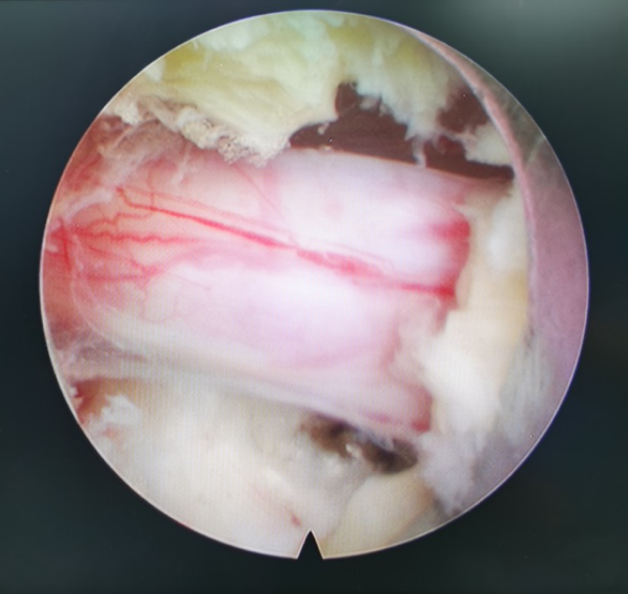

镜下神经根松解良好

摘除突出椎间盘组织